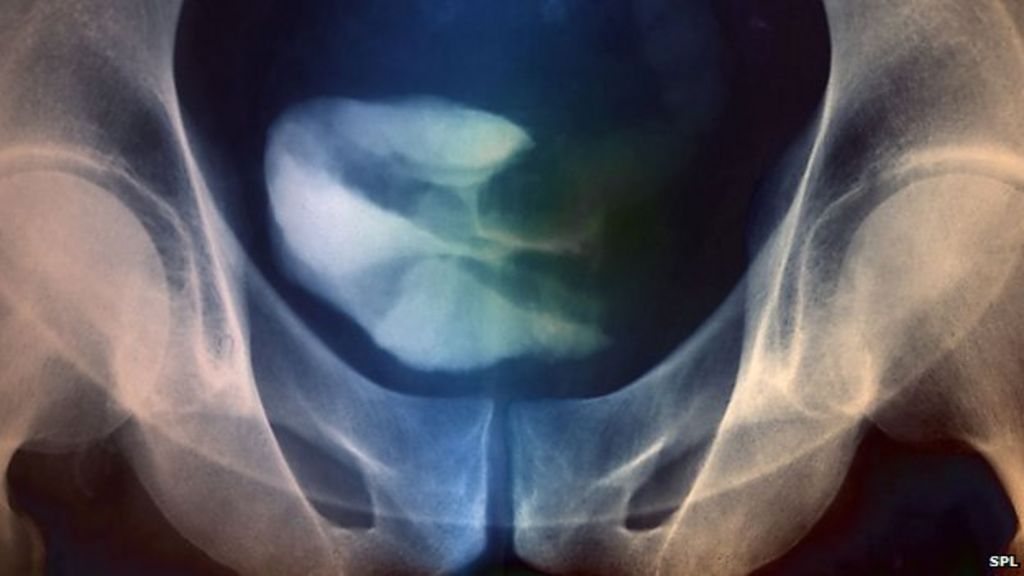

50+ Bladder Ulcers Cancer Pics. As more cancer cells develop, they can form a tumor and, with time, spread to other parts of the body. Management of bladder cancer is strongly determined by the classification of the cancer.

Most bladder cancers start in the innermost lining of the bladder. For bladder cancer, the stage is determined based on examining the sample removed during a turbt (see diagnosis) and finding out whether the cancer has spread to other parts of the body. The tumour can also spread.

Bladder cancer is the fourth most common cancer in males, but it can also affect females.